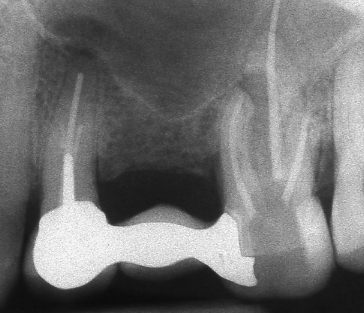

Оралната хирургия е дял от денталната медицина. Понятието орална хирургия е доста условно - с него се обозначават различни видове оперативни интервенции в областта на устната кухина, въпреки че дори и почистването на един кариес по своята същност представлява оперативна интервенция (некректомия); екстирпацията на един нерв от зъбен канал, почистването на зъбен камък, пиленето на зъб за корона и запълването на коренов канал също са оперативни интервенции, понякога технически доста сложни. Все пак всички тези манипулации са извън обема на оралната хирургия - тя включва екстракцията на ретинирани зъби, отстраняването на кисти от зъбен произход, на малки по обем доброкачествени тумори, и, разбира се, поставянето на зъбни импланти. Всички необходими манипулации за осъществяването на костна пластика при имплантатите също влизат в обема на оралната хирургия.